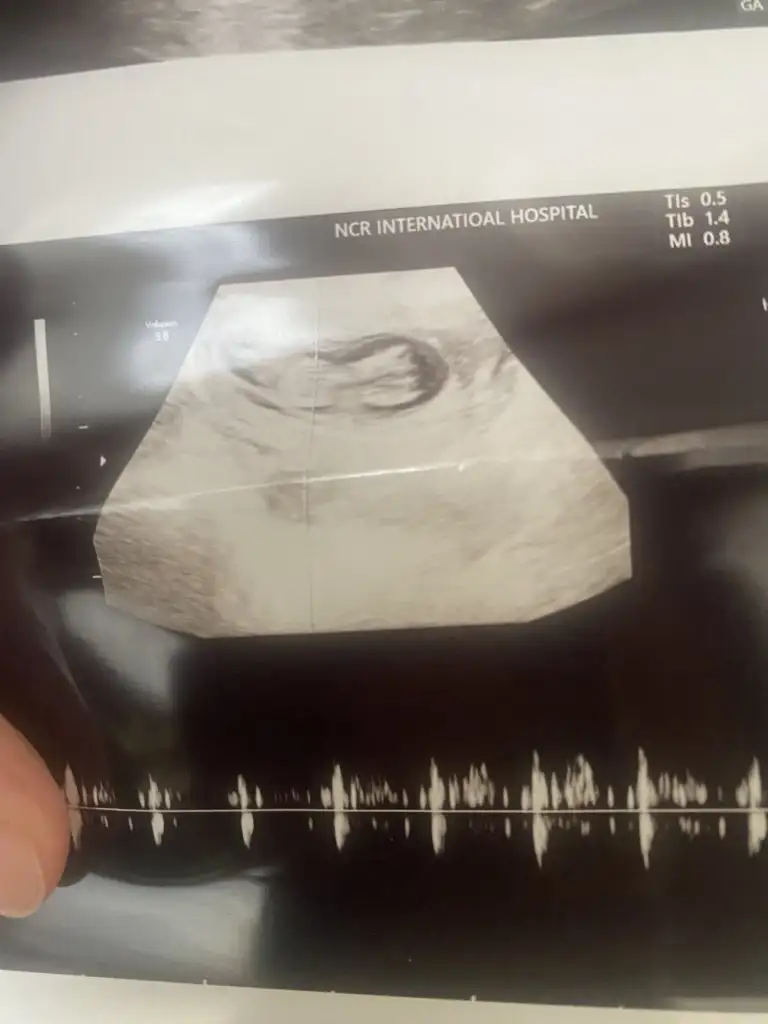

Kizlaaaat bizede tahminde bulunur musunuz doktor ilk kız dedi sonra çıkıntı görüyorum erkek dedi

yaa bende şuan 20.haftadayım 13.haftada kız dedi doktorum 15 ve 16 da da erkeğe benziyor ama kordon da olabilir dedi organ taramada netleşir dedi salı günü gideceğiz ona da insan merak ediyor tabi